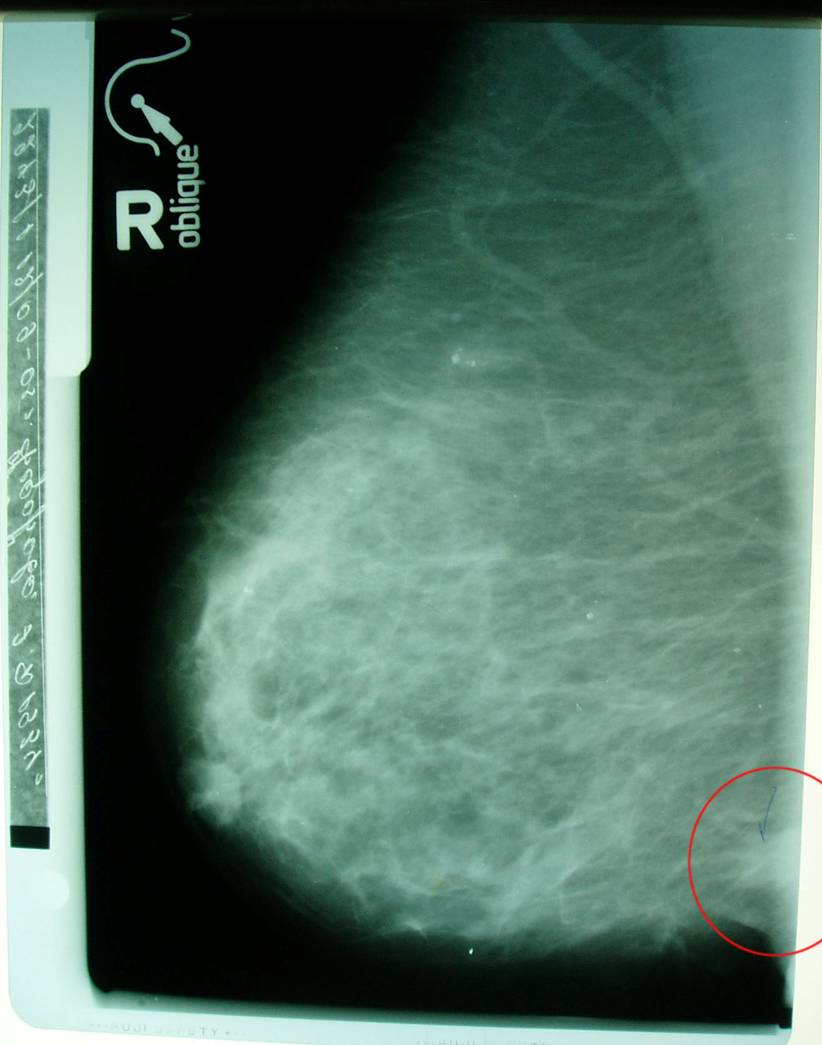

Маммограмма в динамике.

Больная раком правой молочной железы T4аN0M0. Регресс.

14.03.2006 (после 6 месяцев траволечения)